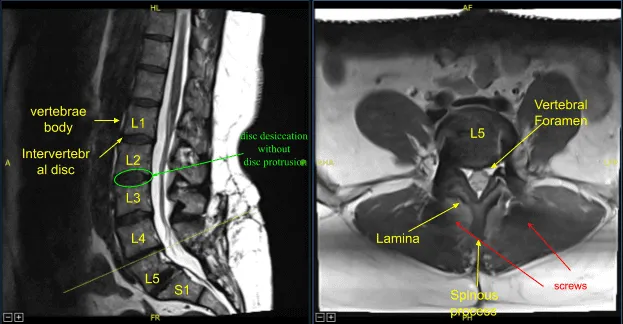

The patient presented to the office status post two previous lumbar surgeries performed by another provider including L5-S1 discectomy and L5-S1 TLIF. They developed recurrent back and lower extremity pain and symptoms and imaging showed adjacent segment disease with L4-L5 disc herniation, stenosis, as well as pseudarthrosis at L5-S1.

Next, we performed L4 laminectomy, bilateral facetectomy with Leksell rongeur, electric high-speed drill under continuous irrigation and Kerrison rongeurs resecting ligamentum flavum in piecemeal fashion and exposed thecal sac, decompressed it circumferentially and neurolyzed bilateral L4 nerve roots with Metzenbaum Penfield technique and confirmed with nerve hooks. Epidural bleeding was controlled with bipolar electrocautery and Surgiflo hemostatic matrix.

The thecal sac was retracted medially towards the right side with nerve root retractor. Annulotomy was performed with a 15-blade scalpel. Discectomy was performed with sequential pedal shavers and pituitary rongeurs. Endplates were prepped for arthrodesis with scrapers. We collected morselized autograft, bone shavings, and morselized resected spinous process and lamina.